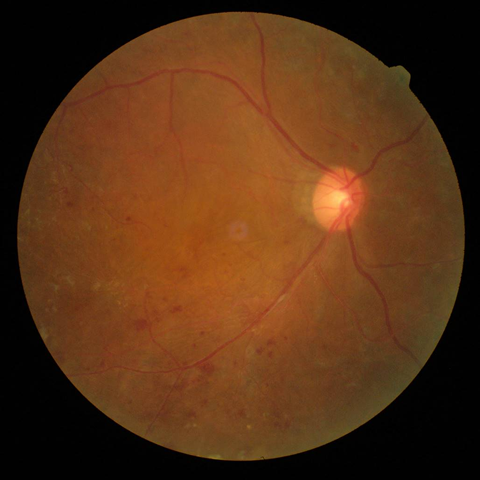

2.前増殖糖尿病網膜症

| 病期 | 症状 | 治療法 |

|---|---|---|

| 中期の網膜症 | 毛細血管がつまり血管閉塞を生じます。血管閉塞した網膜は虚血におちいり、軟性白斑という所見が生じます。 | 虚血網膜は放置することによって、新生血管が生じ、硝子体出血や増殖膜のもとになるため、この段階で、的確なレーザー治療(網膜光凝固術)をしっかりと行っておくことが非常に重要になります。 |

軟性白斑 |

レーザー光凝固施行前の糖尿病網膜症  レーザー光凝固施行後の糖尿病網膜症 |